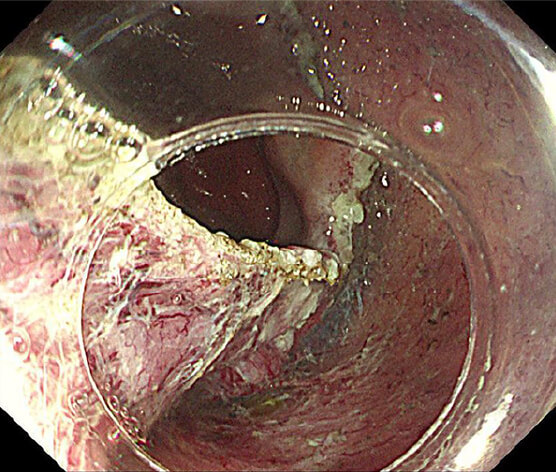

光線力学的療法(PDT)

放射線療法後の遺残再発食道癌に対する光線力学的療法(PDT)も行っており、PDTの実施可能施設は九州で4施設のみ、長崎県内では当院が唯一の実施施設となっています。

治療前

PDT

PDT 5ヶ月後